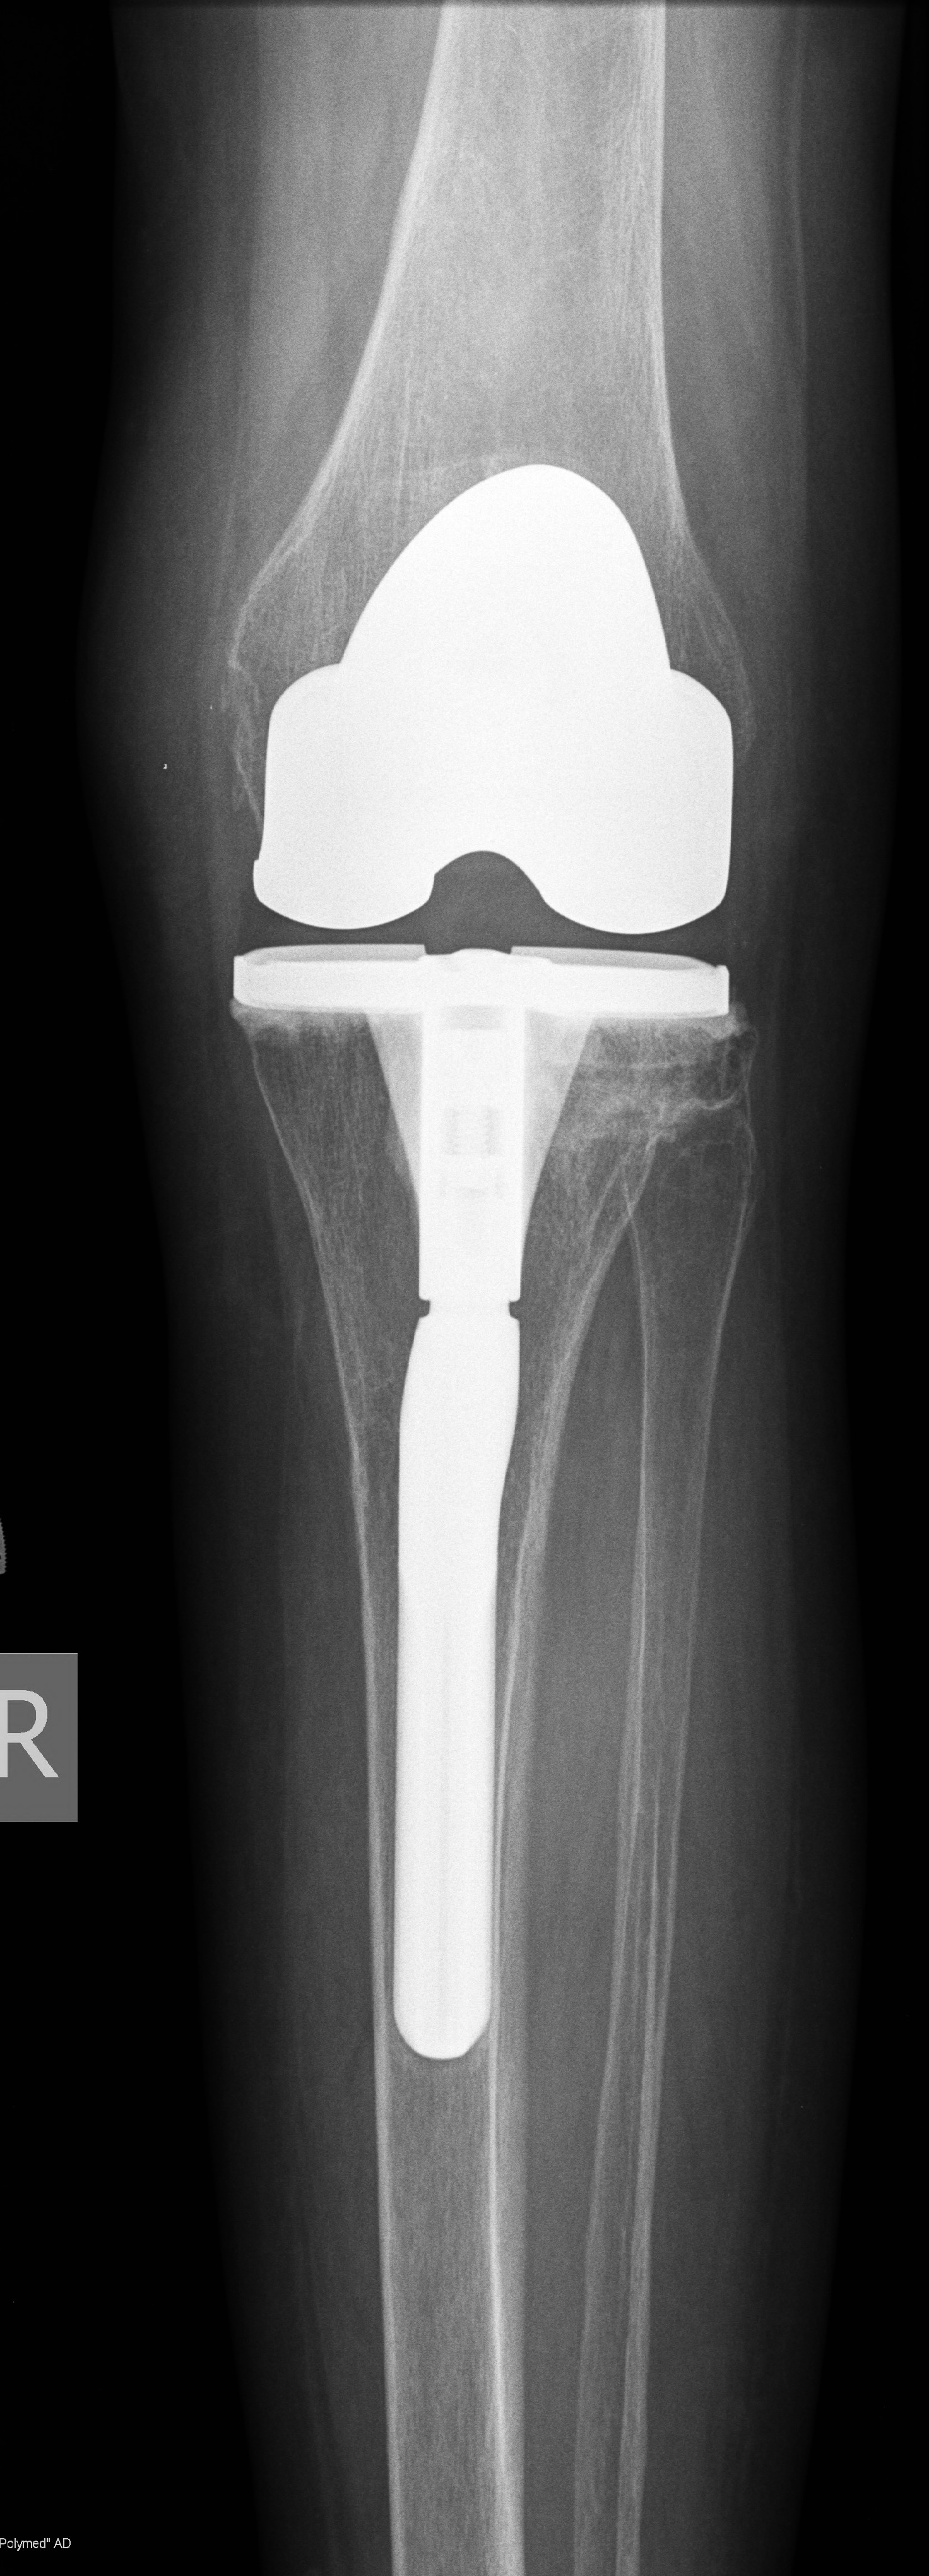

- Ендопротезиране на колянна и тазобедрена става

Основно лекувам заболявания на тазобедрена и колянна става чрез минимално инвазивно ендопротезиране, следтравматични и дегенеративни нарушения на ръката и китката и халукс валгус (популярен като „кокалчета на краката”).